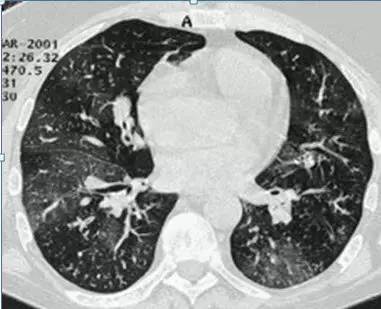

肺磨玻璃影(GGO,ground glass opacity)在胸部 CT 表现为密度轻度增高的云雾状淡薄影/圆形结节,样子像磨砂玻璃一样,所以叫磨玻璃影。

GGO 可以是弥漫性散在生长,也可以仅聚集在局部,看起来像一个小磨玻璃结节。一般而言,弥漫性生长的多数是良性病变,局灶性生长的容易不好。

在更多的时候 GGO 是恶性的。